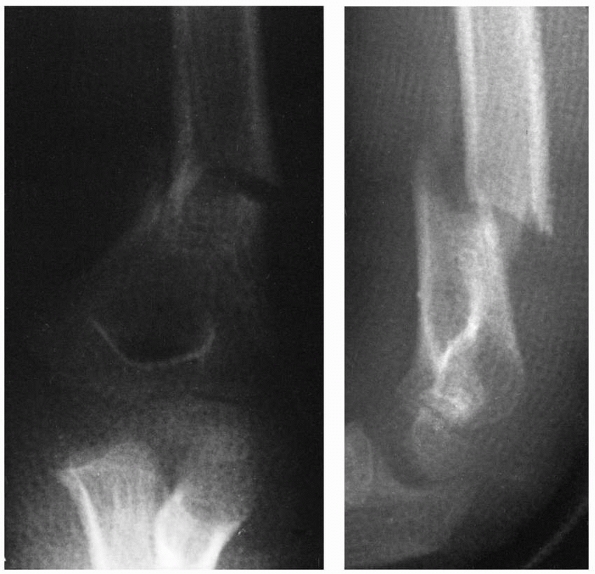

is common in children and adolescents. The child who presents with

shoulder dislocation without a clear history of trauma should arouse

suspicion that atraumatic instability may be present. These patients

have inherent joint laxity that allows the shoulder to be dislocated

either voluntarily or involuntarily as the result of a minimal

traumatic event (Fig. 17-11).87